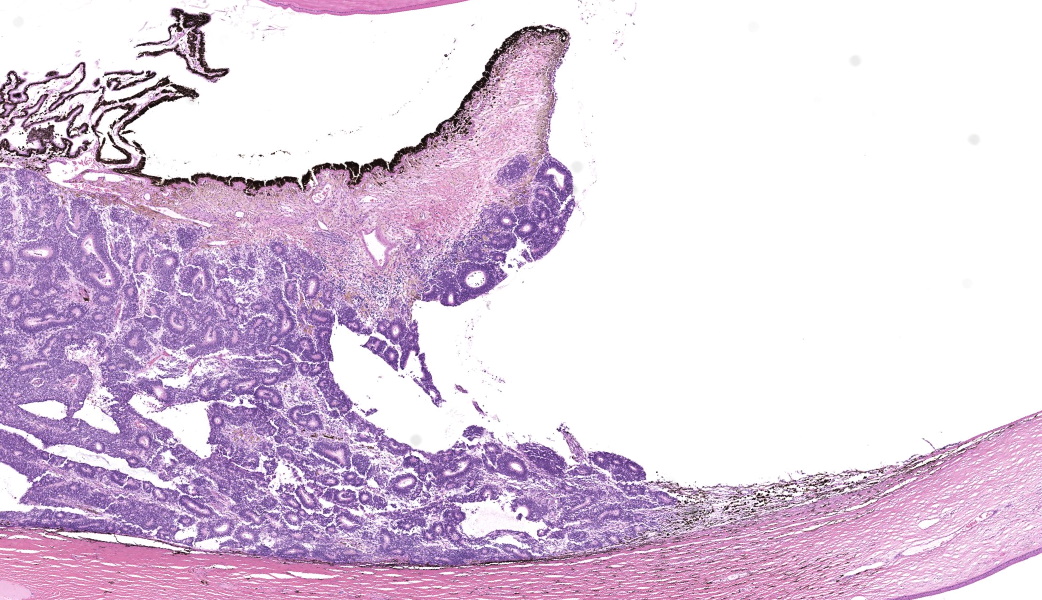

Expanding the anterior uvea, effacing the iris, and markedly expanding the suprachoroidal space is a densely cellular, unencapsulated neoplasm of neuroepithelial cells. Neoplastic cells are arranged in variably dense sheets and as palisading columnar cells surrounding a central lumen (Flexner-Wintersteiner rosettes) or surrounding eosinophilic fibrillar material (Homer-Wright rosettes) surrounded by collagenous and occasionally myxomatous stroma. Neoplastic cells are polygonal to fusiform, have a high nuclear to cytoplasmic ratio, and have distinct cell borders. The nuclei are round to ovoid, finely stippled, and have indistinct nucleoli. There are 16 mitoses in 10 high power fields and anisokaryosis is mild. The neoplastic cells are impinging upon the optic nerve, which has multifocal axonal degeneration and is infiltrated by a population of histiocytes, lymphocytes, and plasma cells, as well as scattered foci of hemorrhage. The retina has multifocal, disorderly components of viable photoreceptor and retinal ganglion cells, dense necrosis, glial scarring, and presumed Mueller cells. The retina is diffusely detached and lacks apparent retinal vessels. The retinal pigment epithelial cells have multifocally migrated through to the inner layers of the retina. The cortical lens fibers are moderately liquefied and homogenous and there is posterior migration of the lens epithelium, consistent with cataractous change. The corneal epithelium has marked, segmental ulceration and the outer corneal stroma in this area is mineralized with occasional breaks and is densely compact with fibrosis. Multifocally throughout the corneal stroma are areas of fibrosis, vascularization, and scattered neutrophils.Contributor's Morphologic Diagnoses:

Eye: Medulloepithelioma, Cataractous change, Ulcerative and neutrophilic keratitis, Stromal fibrosis and mineralization, Diffuse, severe retinal atrophy, Suspect avascular retina, Moderate optic nerve degeneration and necrosis.Contributor's Comment:

Medulloepitheliomas classically present grossly as white to tan masses that fill the posterior chamber. The hallmark feature of primitive neuroectodermal tumors is the formation of rosettes. This tumor forms both Flexner-Wintersteiner rosettes (characterized by the formation of a central lumen) and Homer-Wright rosettes (characterized by the lack of central lumen and may surround eosinophilic fibrillar material).10 Importantly, the formation of both rosettes is found in other primitive neuroectoderm tumors and is not unique for medulloepitheliomas. Retinoblastoma is a similar primitive neuroectodermal tumor and must be differentiated histologically from medulloepitheliomas. In retinoblastomas, although they may occasionally have both types of rosettes, Flexner-Wintersteiner rosettes are often the dominant type. While retinoblastomas are common ocular tumors in young children, there are very few accounts of this diagnosis in veterinary species.5 Characteristically, rosettes in a medulloepithelioma are often large, multi-layered and lined by cuboidal cells arranged in a right angle to the lumen. There is pronounced neuroepithelial tubule formation, a distinguishing characteristic not found retinoblastomas. Medulloepitheliomas have been described more robustly in veterinary species, and the presence of large, multilayered, Flexner-Wintersteiner and Homer-Wright rosettes ultimately led to the diagnosis of medulloepithelioma in this case.